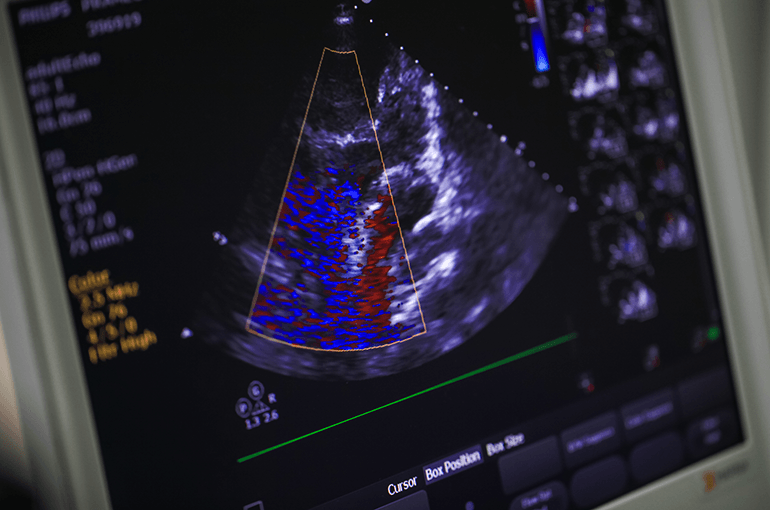

Heart failure is a condition where your heart can’t pump blood around your body as well as it should. It doesn’t mean your heart has stopped working but you may need support to help it work better.